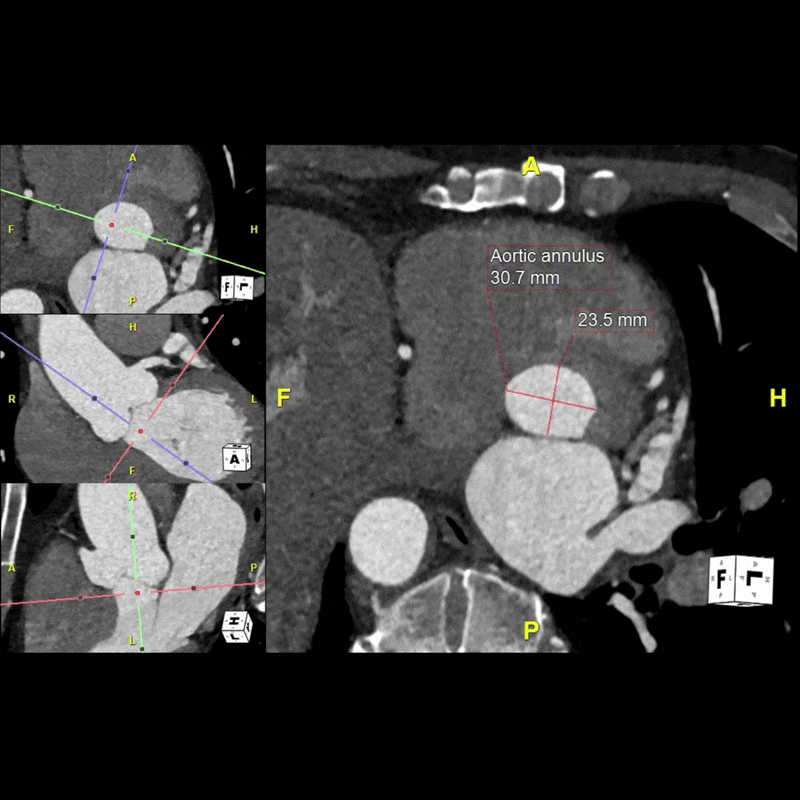

Figure F: Standardized aortic diameter measurements obtained at predetermined locations along the thoracic aorta for surveillance.